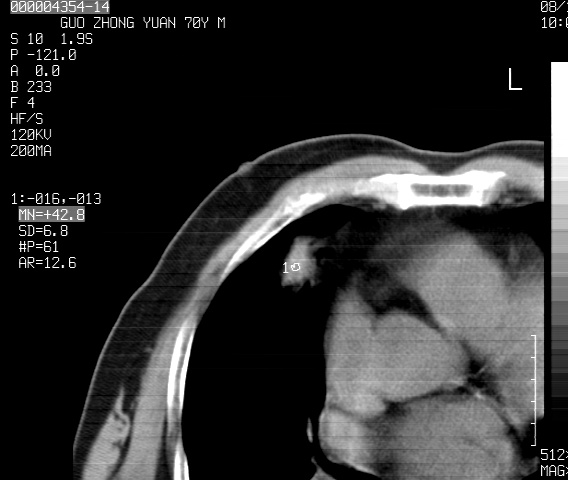

以下是引用sdzyy在2008-12-1 11:49:00的发言:[br]图像不全,请上传,右下肺炎症可能性大,占位待排.

以下是引用zjzjr在2008-12-1 14:53:00的发言:[br]图像不全,请上传,右下肺炎症可能性大,占位待排.心影增大,建议进一步检查.